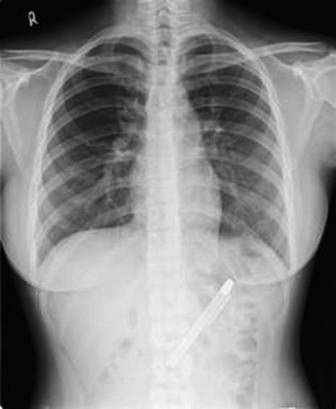

Chiếc bút được phát hiện sau khi bệnh nhân được nội soi và chụp X-Quang.

Các bác sĩ cho biết chiếc bút này đã nằm trong cơ thể bệnh nhân suốt một thời gian dài và đã bị hoen gỉ do môi trường axit trong dạ dày. Nếu chiếc bút không được phát hiện và loại bỏ sớm thì nó có thể gây ra những biến chứng nguy hiểm hơn, thậm chí ảnh hưởng đến tính mạng.